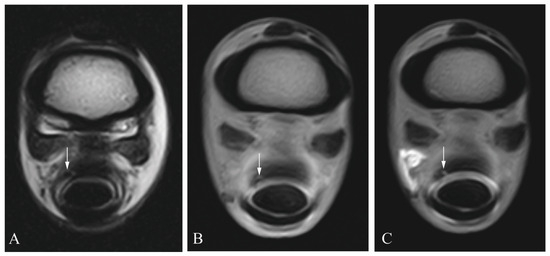

2.3. Diagnostic Imaging

2.4. Image Analysis